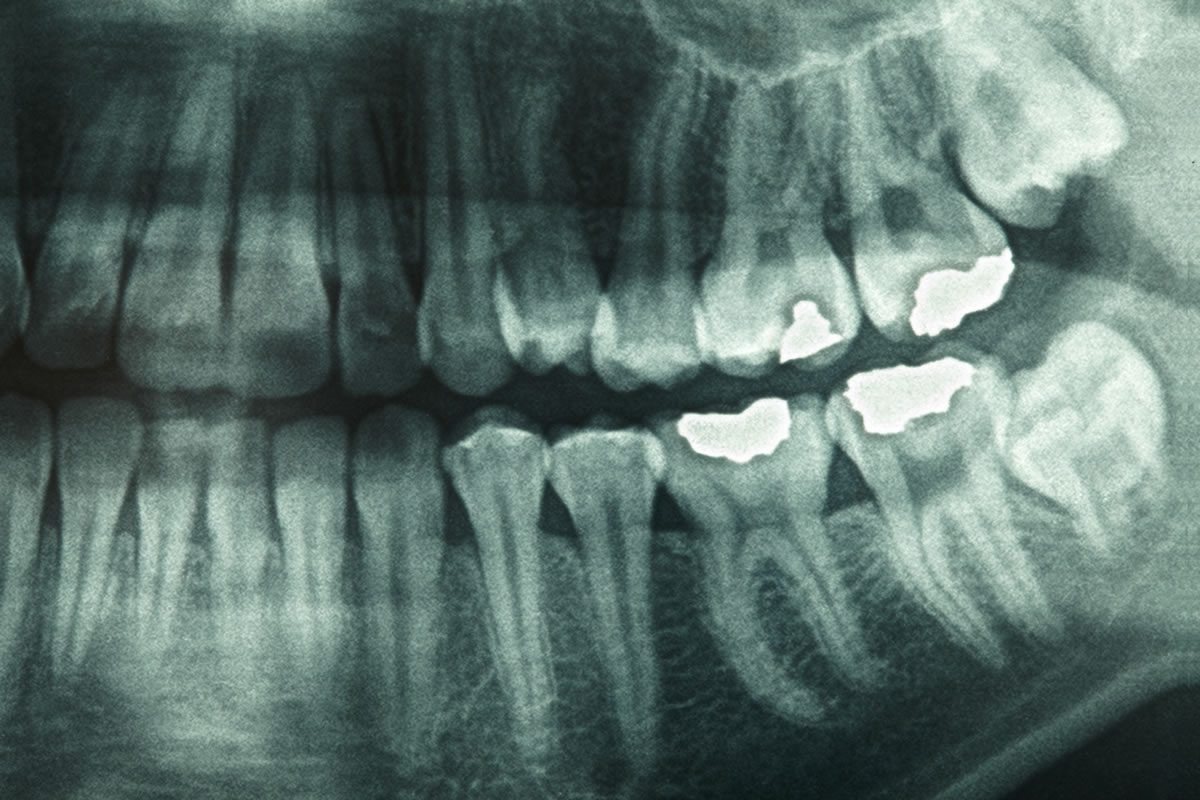

A panoramic X-ray captures the entire mouth in a single image, including the upper and lower jaws, teeth, temporomandibular joints (TMJ), and sinuses. Unlike traditional intraoral X-rays that focus on a few teeth at a time, panoramic X-rays give a holistic view, making it easier to detect abnormalities such as impacted teeth, cysts, tumours, and jaw disorders.

This type of imaging is often recommended for new patients, orthodontic evaluations, wisdom teeth assessment, and planning for dental implants. Its ability to provide a comprehensive picture of oral structures makes it a vital tool in modern dentistry.

Additionally, panoramic X-rays are invaluable for detecting conditions that may go unnoticed with traditional imaging. They can reveal jawbone irregularities, detect early signs of dental disease, and aid in treatment planning for braces or other corrective procedures. The clarity and broad coverage of this technology ensure better preventive care and early intervention.